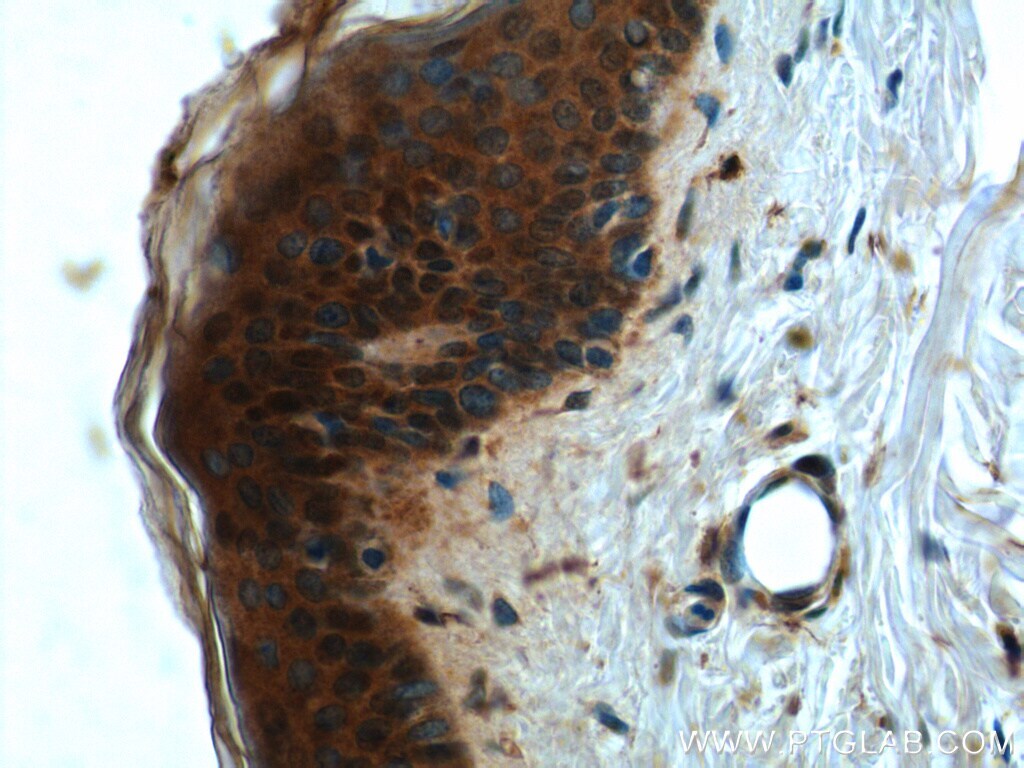

- Submitted by

- Main image

- Experimental details

- Immunohistochemistry of paraffin-embedded human testis tissue slide using 21869-1-AP ( CCHCR1 Antibody) at dilution of 1:50 (under 10x lens).